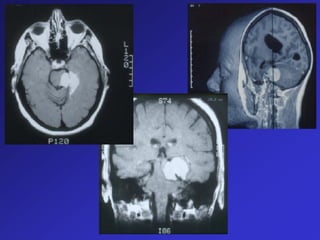

MRI Contrast  Gadoliniumsolution injected into vein  Gadolinium alters the interaction of radio waves with the protons in water so that it gives MORE signal  Shows up as white on images

MRI Contrast

 Gadolinium solution injected into vein

 Gadolinium alters the interaction of radio

waves with the protons in water so that it

gives MORE signal

 Shows up as white on images